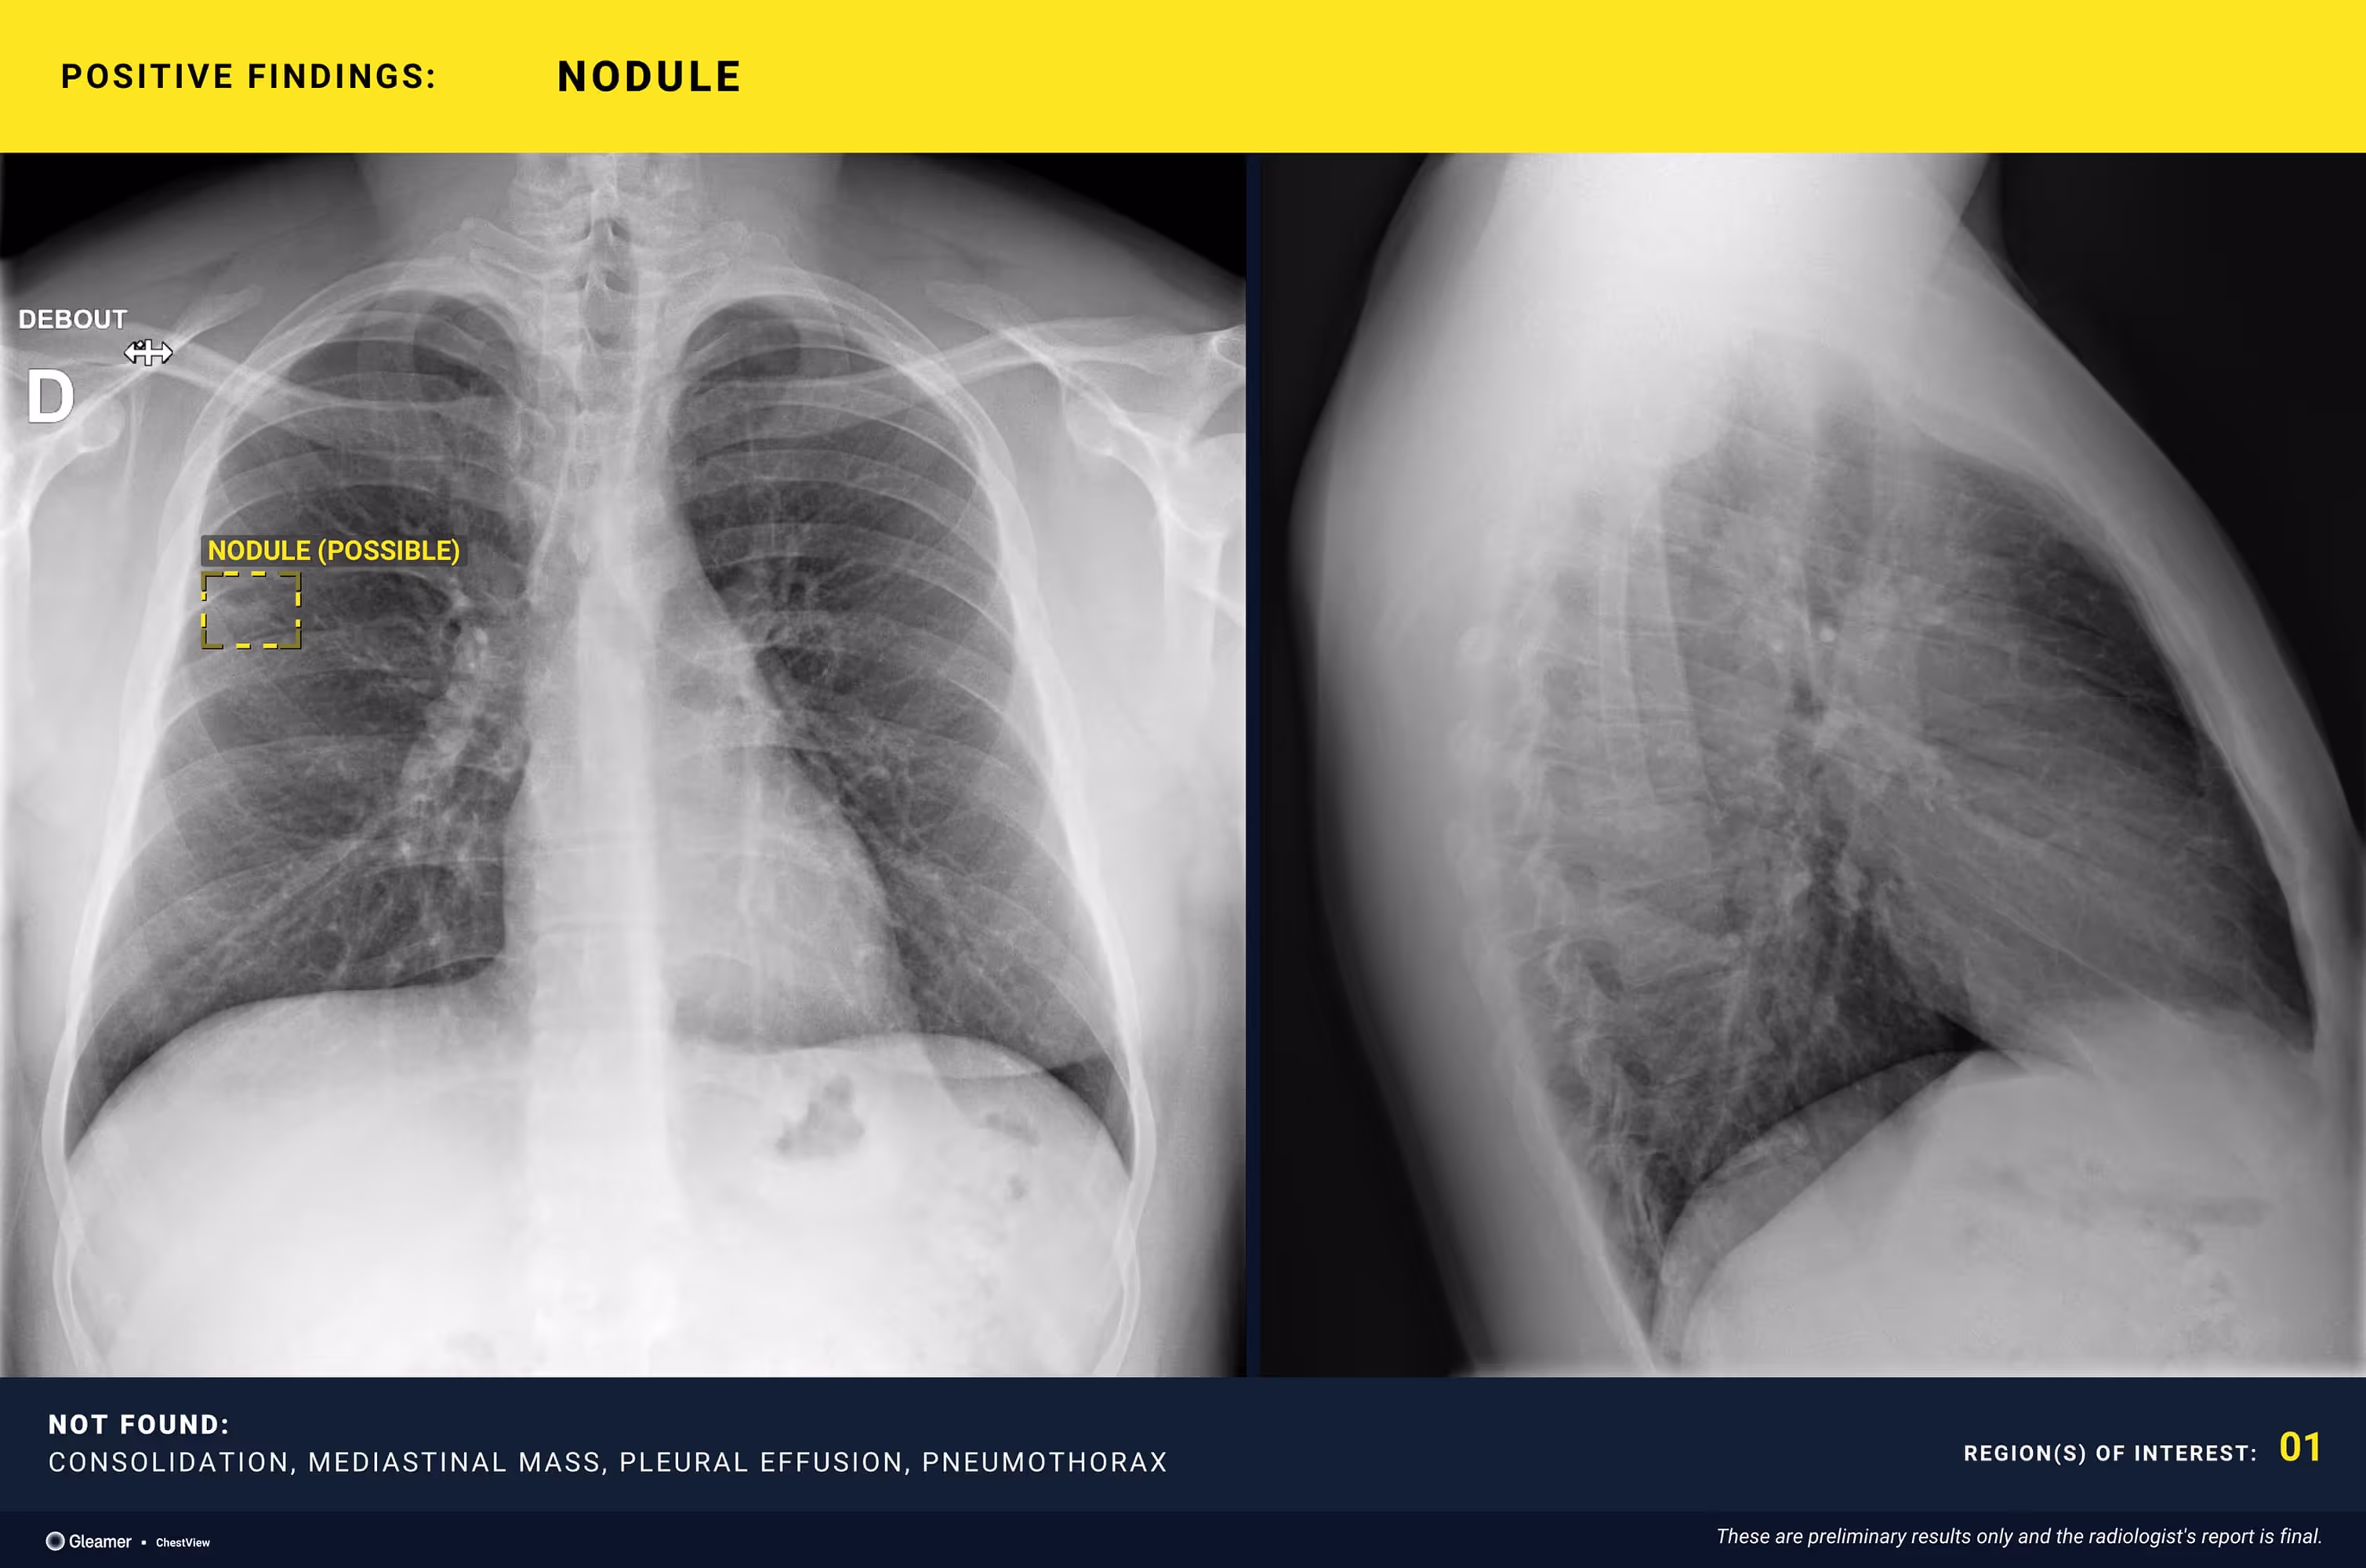

A 26-year-old male smoker with persistent cough.

Results

ChestView detected a suspicious nodule, confirmed by CT.